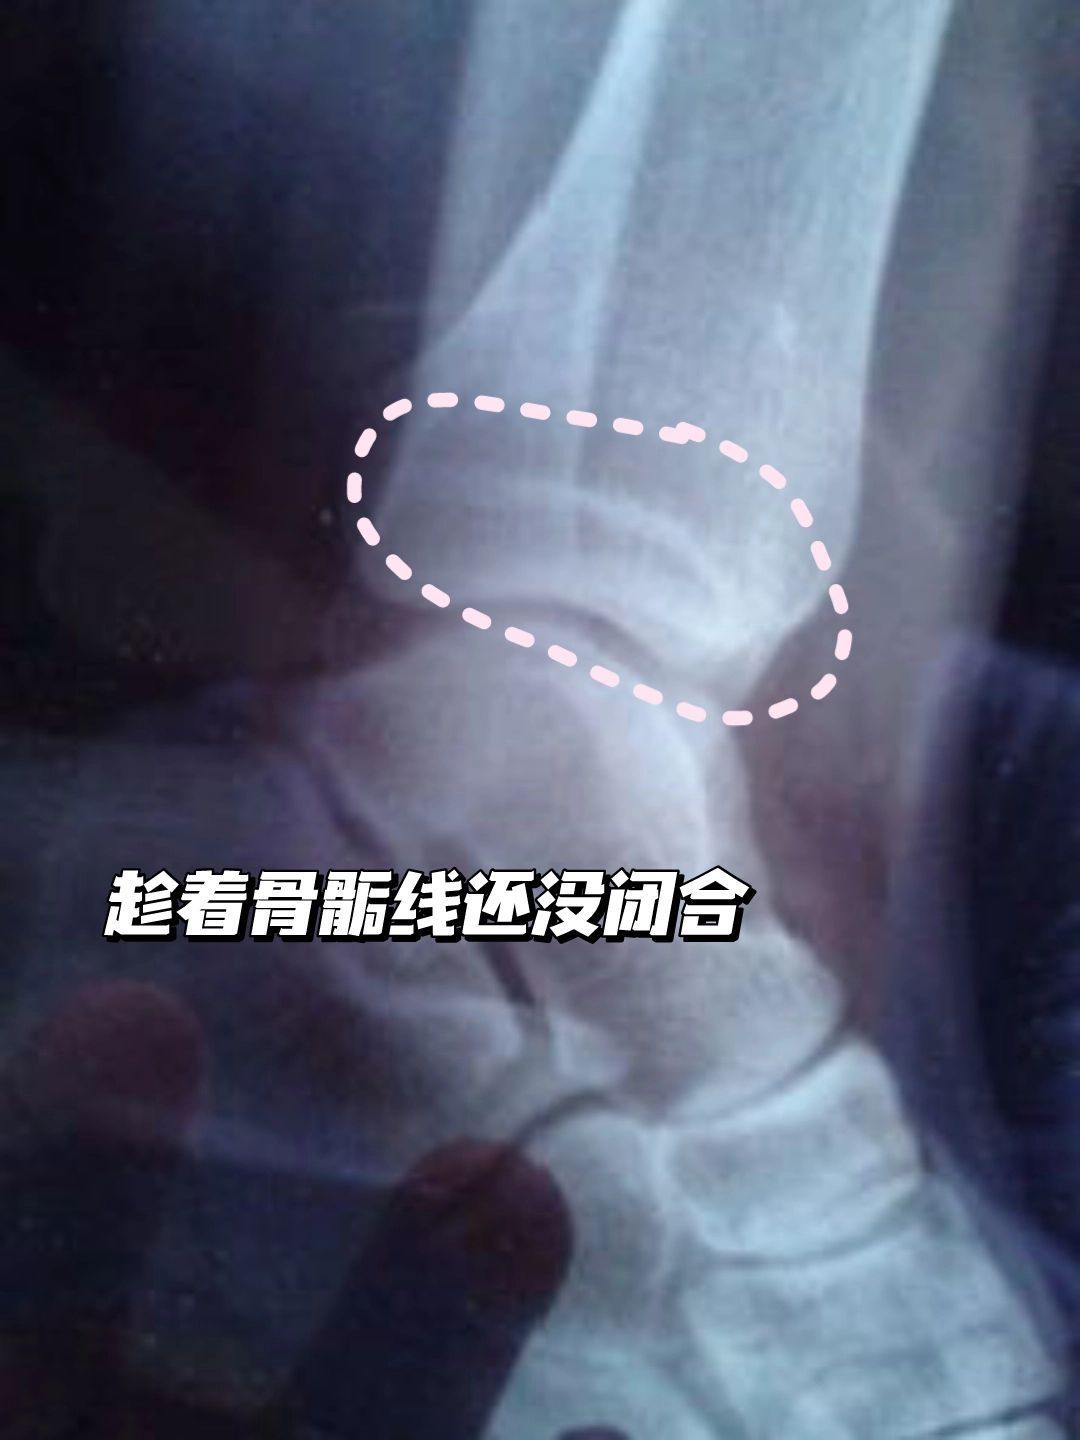

本人男21岁用两个月长高10CM 💟食物方面 多食用小麦胚芽、虾、鸡肉、猪腿肉、牛奶、豆类等富含氨基酸与蛋白质的食物。 少喝果汁、可乐、甜点等(因为这些食物糖分较高,极易影响钙质吸收,若是食用过多此类食物,容易影响骨骼发育) 📝最为重要的四大类; 1⃣️牛奶 牛奶中含有丰富的矿物质钙、磷、铁、锌、铜、锰、钼。最难得的是,牛奶是人体钙的最佳来源,而且钙磷比例非常适当,利于钙的吸收,可以非...